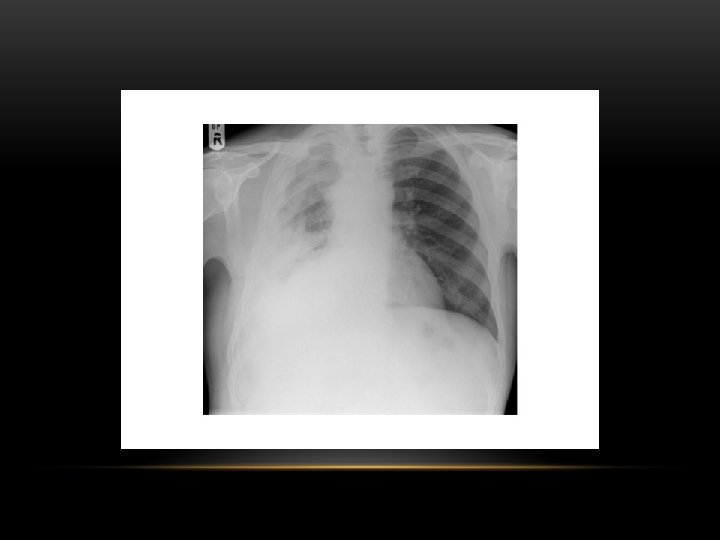

Tension Pneumothorax • No vascular markings on right • Shift of mediastinum to left • Atelectasis right lung • Increased haziness on left: Diversion of entire cardiac output